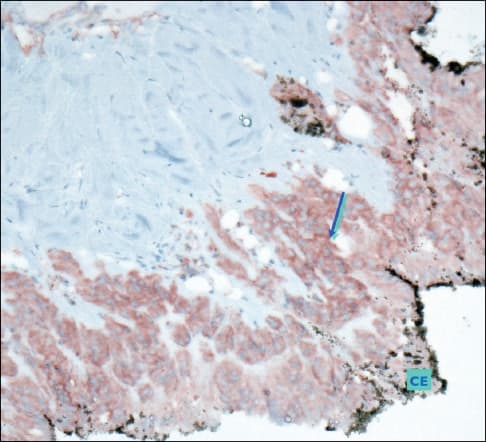

Figure 4. Immunohistochemistry study: case C55. Epithelial growth factor receptor (EGFR) x200. Ciliary epithelium (CE). Overexpression (in red) of EGFR in hyperplasic NPCE (arrow).

Simultaneously, the detached neuroepithelial retinal cells showed neuronal loss with a considerable decrease in NSE+ cells and reactional gliosis with intense expression of glial fibrillary astrocytic protein (GFAP), a marker of mature astrocytes (Figure 5). Additionally, proliferation of retinal pigment epithelium cells, which colonized the retinal surface, was also present, as commonly seen in PVR. Notably, GFAP testing in the CE was negative, indicating that this ciliary proliferation did not present any glial differentiation (Figure 5).